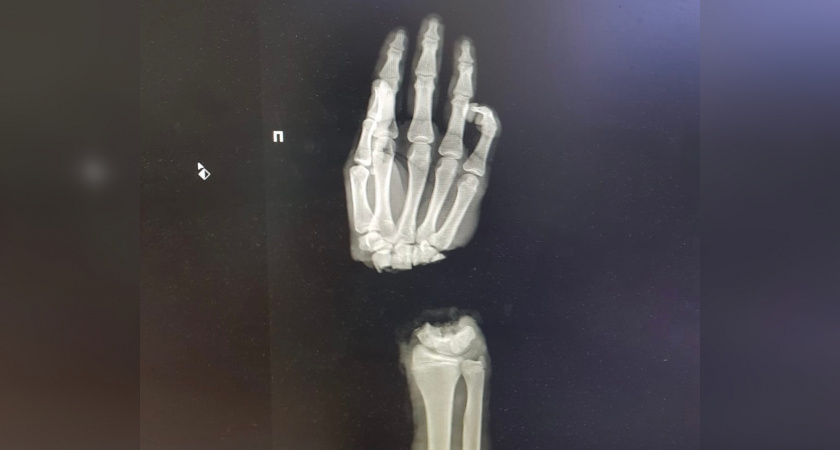

16-летний ковровчанин отрубил себе кисть, пока колол дрова. Подростка с отрубленной кистью привезли в Университетскую клинику еще 1 марта. В тот же день врачи провели операцию по реимплантации конечности.

Сейчас состояние юного ковровчанина стабильное, кровоснабжение кисти было восстановлено.  Но вместе с тем ему понадобится еще несколько операций, чтобы по возможности восстановить функциональность пострадавшей кисти.

Дарья Иудина Фото: Приволжский исследовательский медицинский университет / Николай Карякин